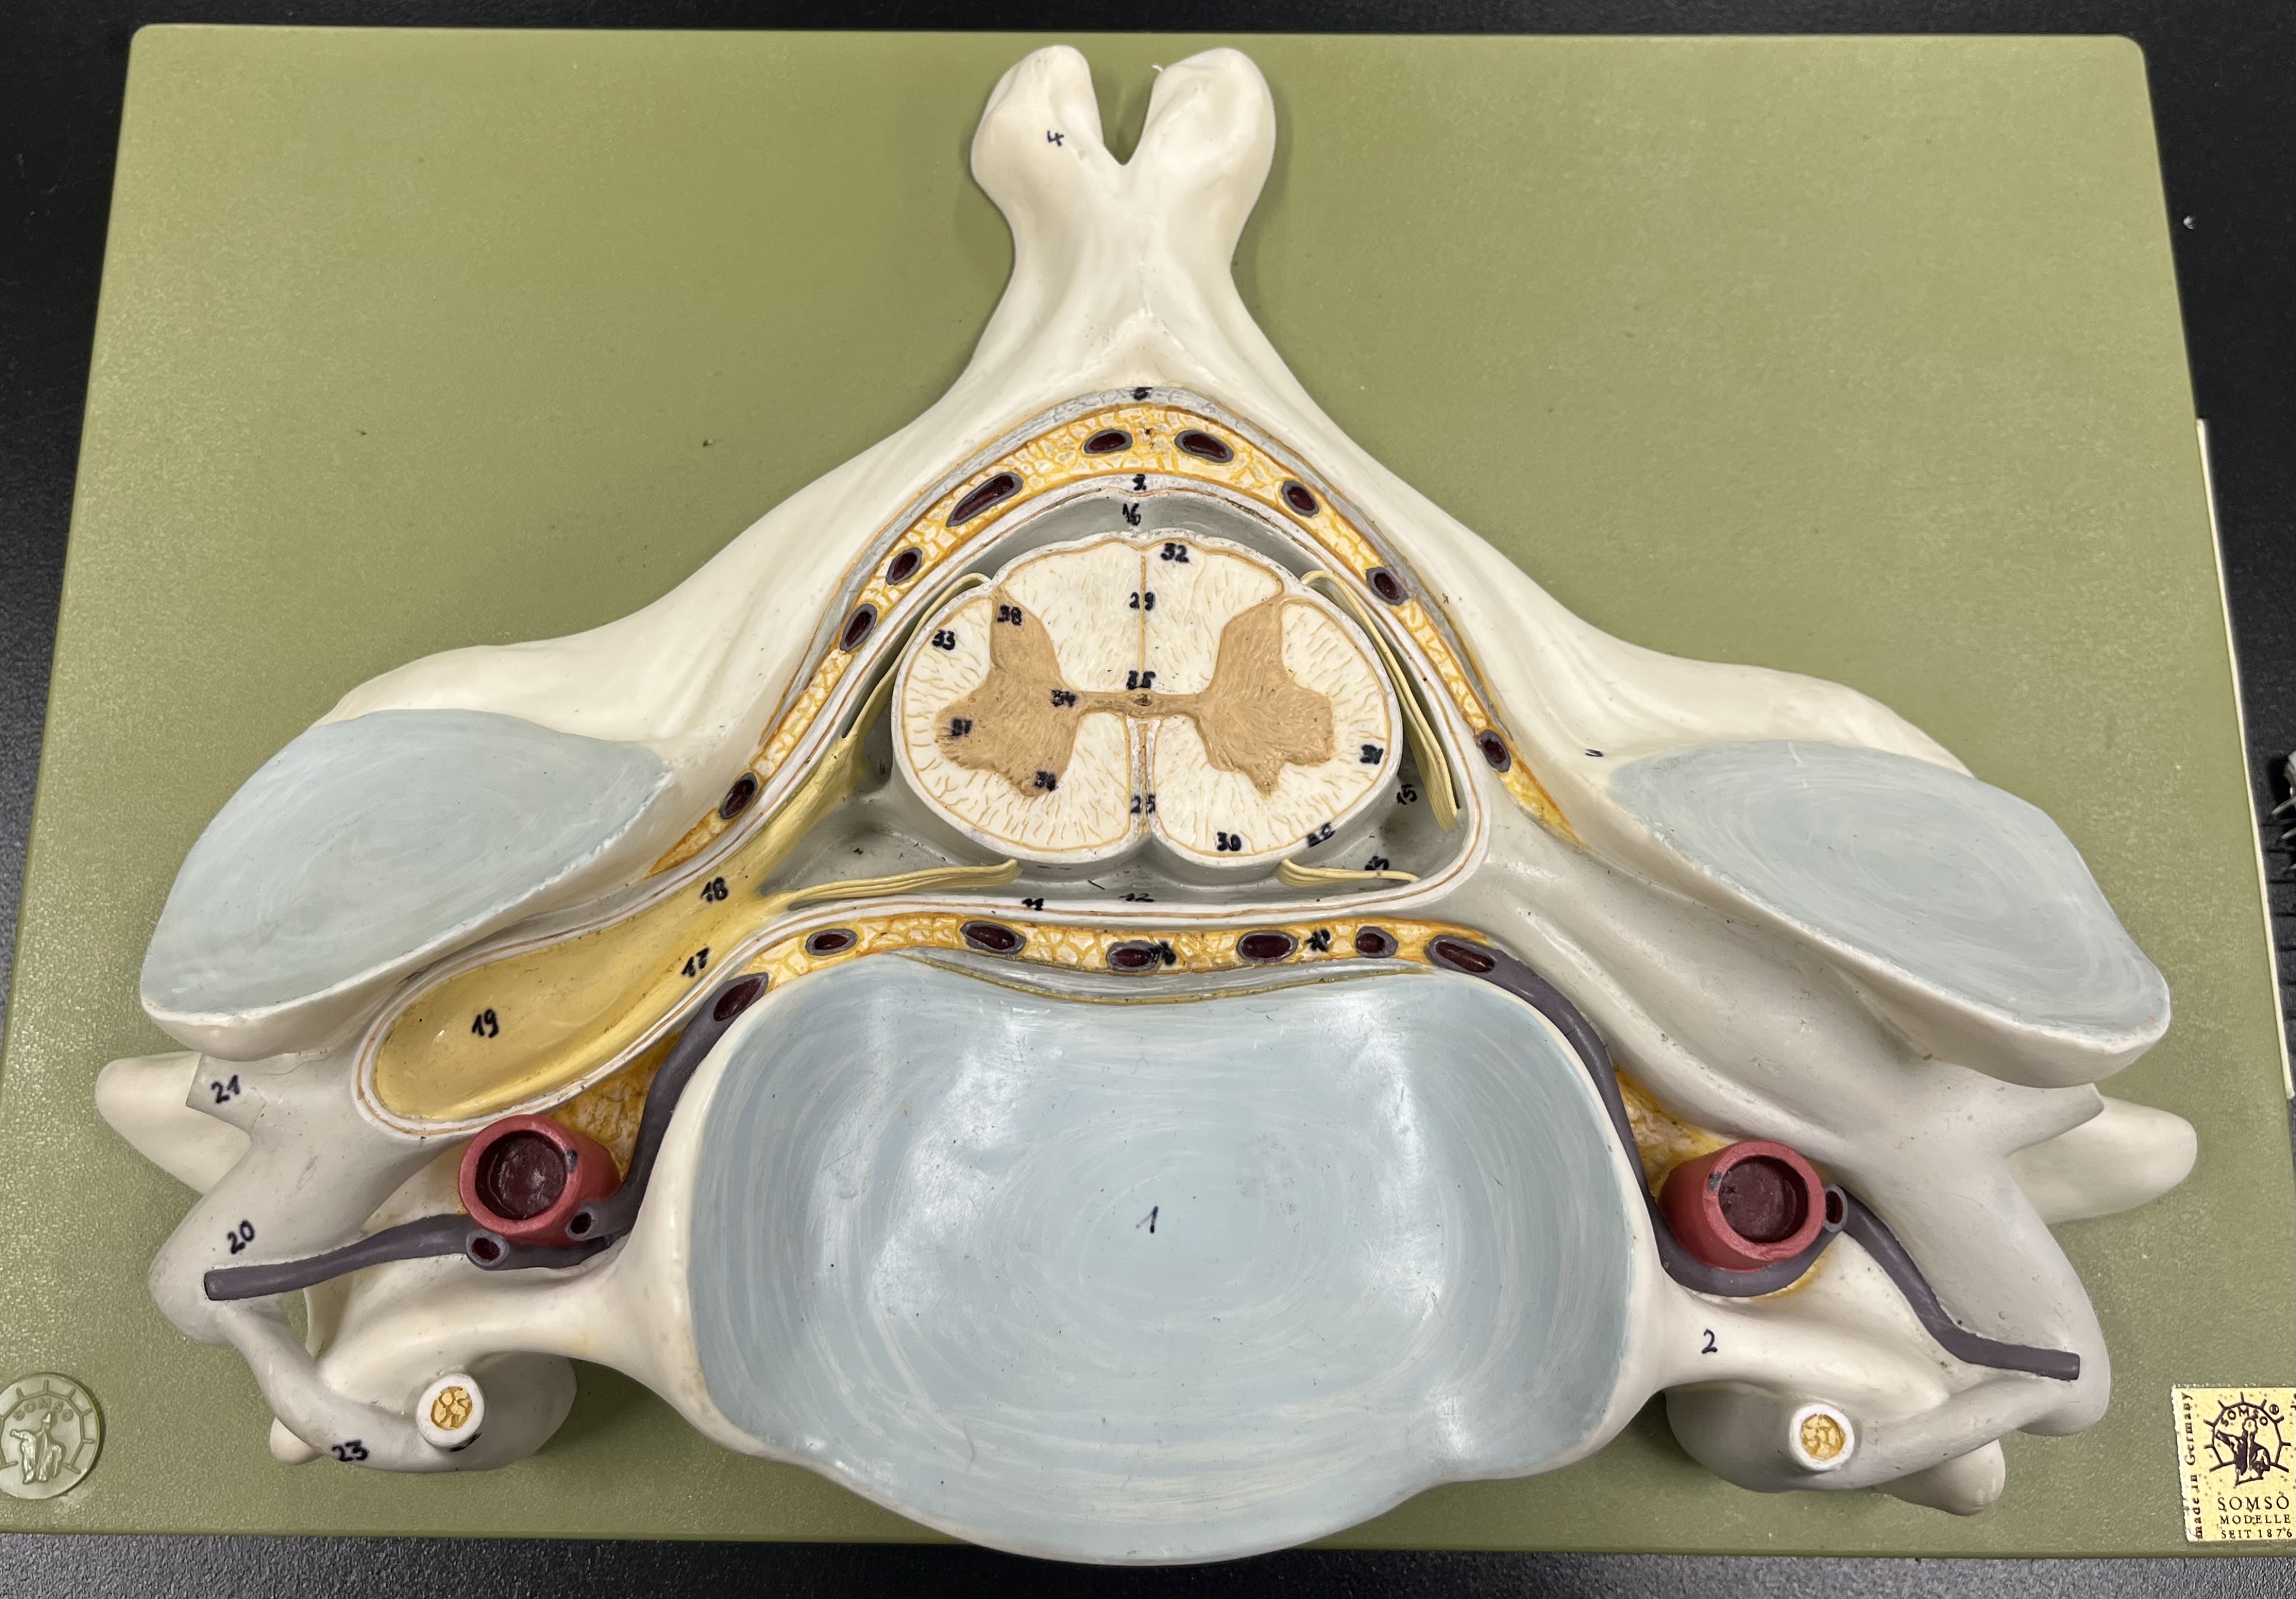

epidural space

dura mater

subdural space

arachnoid mater

subarachnoid space

pia mater

denticulate ligaments

What is the groove here?

anterior median fissure

posterior median sulcus

posterior (dorsal) horn

anterior (ventral) horn

lateral horn (selected models)

gray commissure

central canal

anterior column

lateral column

posterior column

white commissure

posterior (dorsal) root ganglion

What is the bulb here?

posterior (dorsal) root ganglion

posterior (dorsal) root

posterior (dorsal) root

anterior (ventral) root

anterior (ventral) root

dorsal ramus

dorsal ramus

ventral ramus

ventral ramus

rami communicantes

rami communicantes

sympathetic chain ganglia

sympathetic chain ganglia